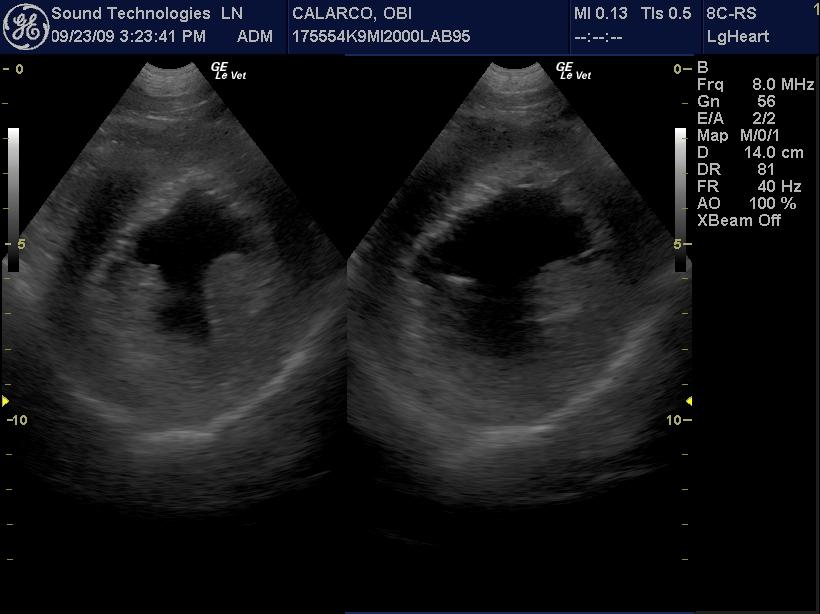

An 11-year-old MN Labrador retriever was prestented for excercise intolerance, lethargy, depression, vomiting and diarrhea. The physical exam was unremarkable other than a grade 2 left sided heart mumur at the heart base and irregular heart beat with pulse deficits. CBC, CHEM, UA, and acth stim were all normal.